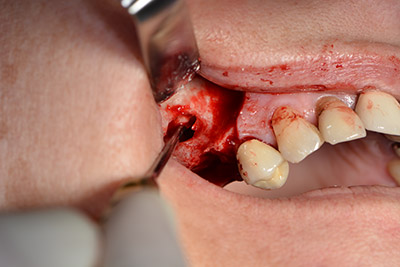

The following holes were drilled at a reduced speed of 300 rpm. The Implantmed demonstrated its true capability at this stage. The surgical protocol can be preset – the various positions can be selected simply by pressing the “P” position of the foot control (Fig. 10 to 11).

The next programmed position is the placement of the implant and in our practice it is preset to a force of 32 Ncm (Fig. 12).